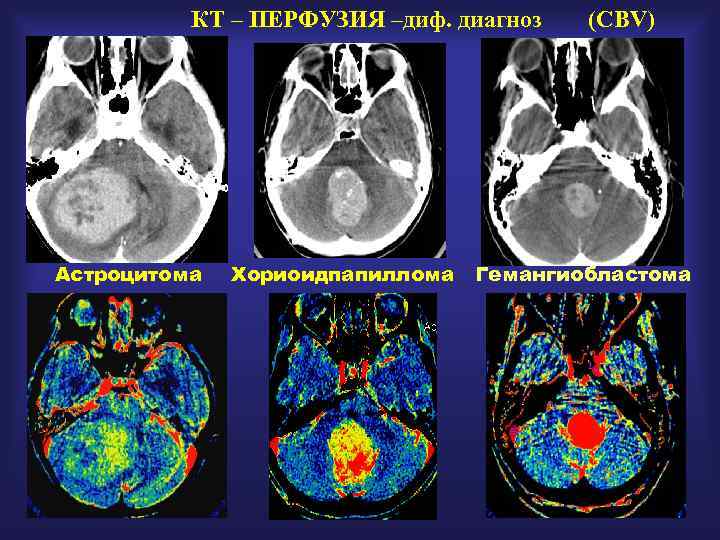

КТ – ПЕРФУЗИЯ –диф. диагноз Астроцитома Хориоидпапиллома (CBV) Гемангиобластома